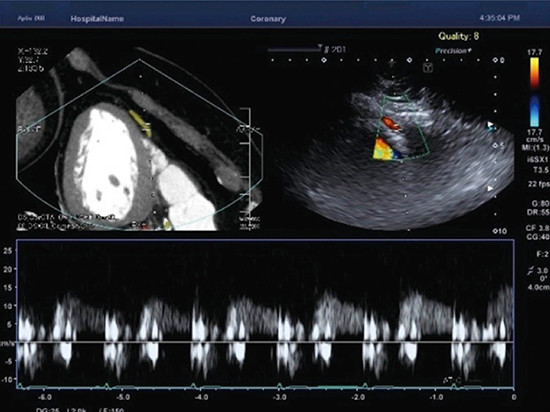

Vitreaに搭載されている冠動脈解析機能では,CT画像の冠動脈を自動でトラッキングし,ラベリングすることができる。Vitreaで冠動脈をセグメンテーションしたCTのデータを超音波診断装置に読み込ませれば,心臓の超音波検査では描出が難しいとされている冠動脈の描出が容易になり,高精度な冠動脈ドプラによる評価を実施できる(図5)。

図5 冠動脈PWD検査をCT画像でガイドした例

(画像ご提供:岡山大学・高谷陽一先生)